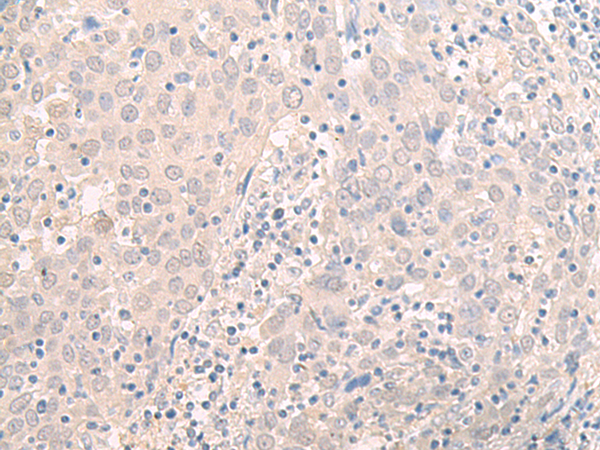

分类: 科研抗体货号: P09795别名: MCAK; CT139; KNSL6应用: IHC反应种属: Human, Mouse, Rat